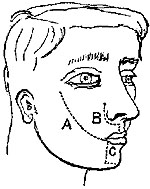

Ligature above Omohyoid.—Using the anterior border of the sterno-mastoid as a guide, but leaving it gradually above to a little nearer the mesial line, an incision (Plate IV. fig. 1), varying in length according to the depth of fat and cellular tissue in the neck, but with its central point opposite the upper border of the cricoid cartilage, must be made through skin, platysma, and superficial fascia. While making the incision the head should be held back, and the face slightly turned to the opposite side; the parts being now relaxed by position, the edges of the wound must be held apart by blunt hooks or copper spatulæ, and the deep fascia carefully divided over the vessel, which will be recognised by the pulsation. It may be noted here that even in thin subjects the sterno-mastoid edge invariably overlaps the vessel, though in many anatomical diagrams it would appear to be in part subcutaneous.

1. Ligature of External Carotid.—Head in same position as for the common carotid. A straight incision parallel with the anterior edge of sterno-mastoid, but about half an inch in front of it, must begin almost at angle of jaw, and extend downwards nearly to the level of the thyroid cartilage. Cautiously divide skin, platysma, and fascia; the lower end of the parotid must be pulled upwards, and the veins, which are numerous, cautiously separated. The anterior border of the sterno-mastoid must be pulled backwards, and the digastric and stylo-hyoid forwards and inwards. The superior laryngeal nerve which lies behind the vessel must be avoided.

2. Ligature of Lingual.—To secure this vessel either before it becomes concealed by the hyo-glossus, or after it is under the muscle, a curved incision is necessary, following the line of the hyoid bone, and especially of its greater cornu, but a line or two above its upper border. After the skin and platysma are divided, the posterior belly of the digastric must be{33} recognised, which again will guide to the posterior edge of the hyo-glossus. The edge of the sub-maxillary gland may very probably require to be raised out of the way. The artery can then be secured, either before it dips under the hyo-glossus muscle, or after it has done so, by the division of a few of its fibres on a director. Care is needed to avoid injury of the hypo-glossal nerve, which lies above the muscle.